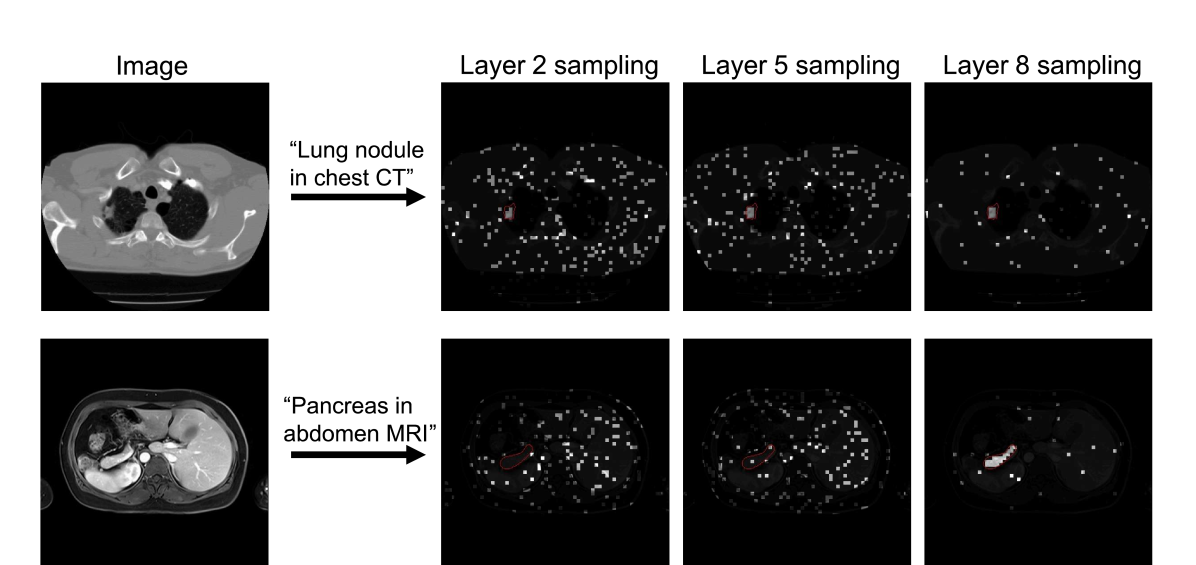

Refer to caption

Figure 4: Examples of Boltzmann sampling from the intermediate layers during inference. For each image and text prompt, the queries only attend to the samples patches at each layer. The dark region is completely masked out in that layer. Boundaries of the ground truth object is marked in red.

4.4 Visualization of Boltzmann attention sampling

In Fig. 4 we show the two examples of Boltzmann attention sampling during text prompt segmentation inference. The query only attends to the visual features on the sampled patches. The sampling is spread out at the earlier layers, for the model to explore the image features. In the middle layers, BoltzFormer begins to exhaust the features in the target region, while continuing to explore other parts of the image. The sampling is highly concentrated on the target regions when getting close to the last layer to refine the prediction with the most relevant features.

Note that in the second example, the query didn’t attend to any feature from the target region until layer 5, however, after that the model quickly focused on the target region.